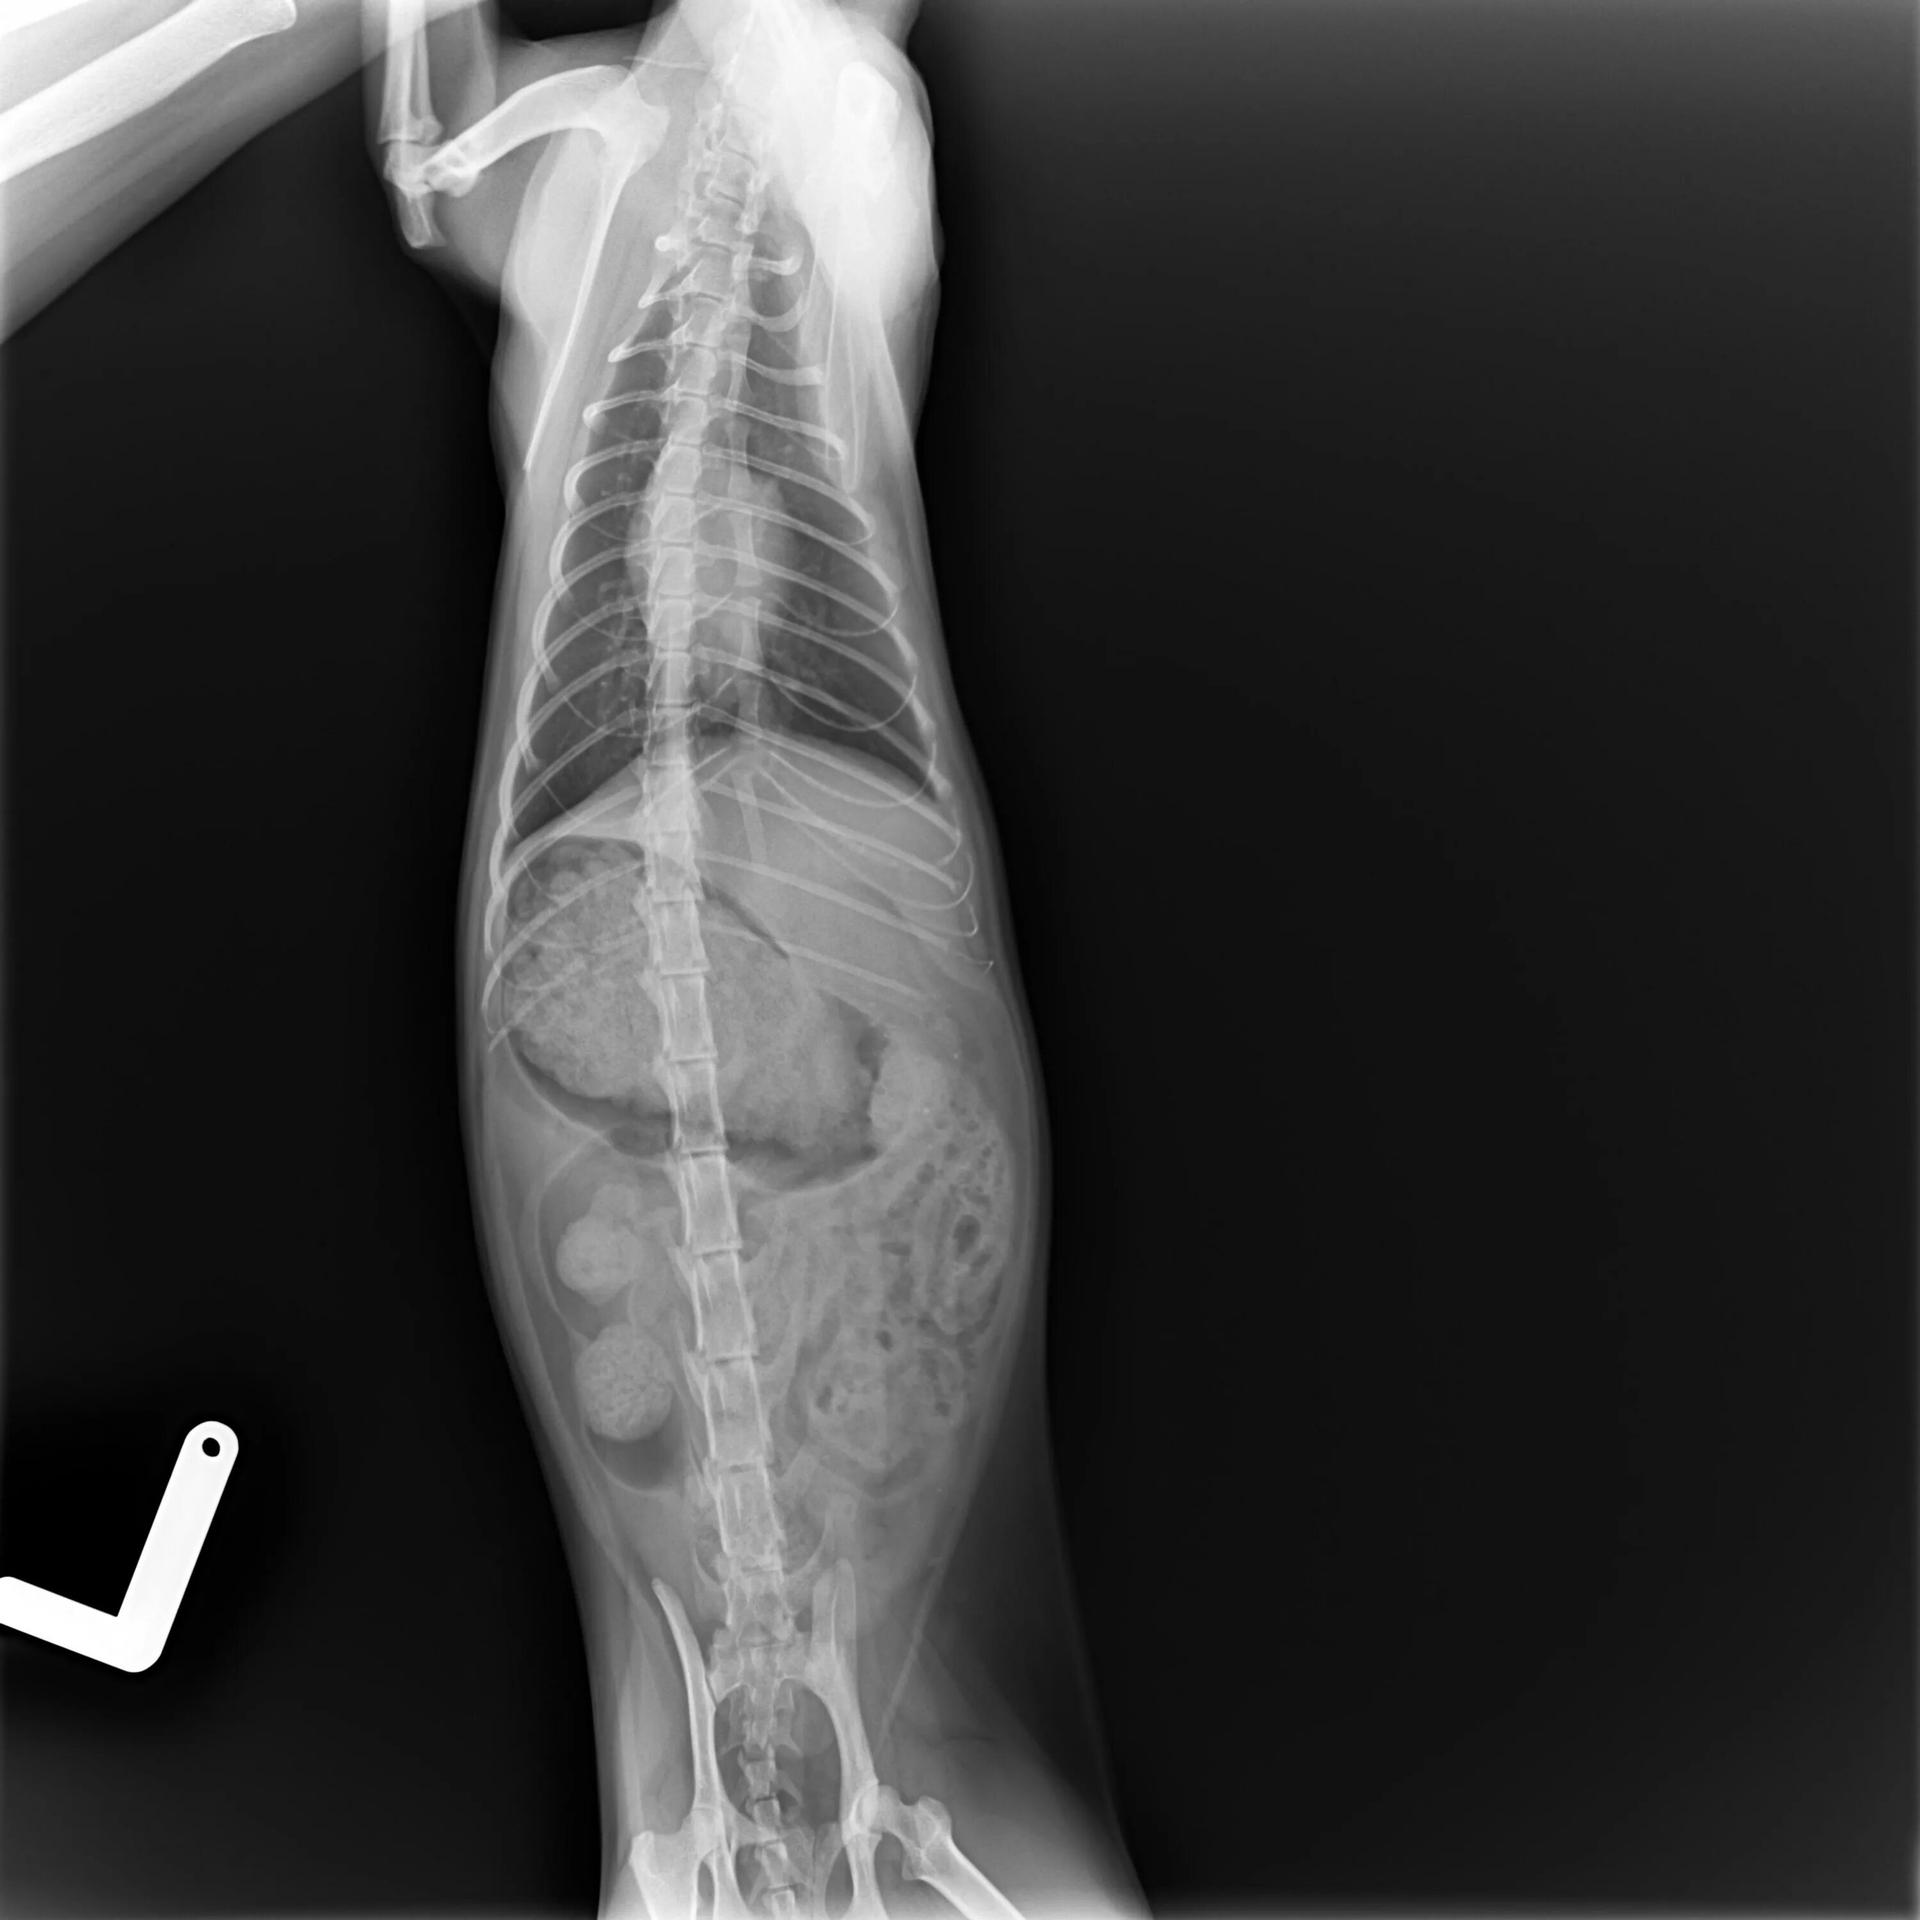

Рентгеновский эффект создает фантастические композиции в этих фотографиях девушки, чье тело становится прозрачным, демонстрируя скелет и внутренние органы. Она позирует в разных позах, ее силуэт светится загадочным свечением. Каждый кадр передает атмосферу научной фантастики и медицинского искусства. Ее кожа кажется полупрозрачной, позволяя увидеть кости и мышцы. Фотографии рассказывают о хрупкости человеческого тела и его внутренней красоте. Девушка то стоит в задумчивости, то делает грациозное движение. Эти иллюстрации вдохновляют на размышления о человеческой анатомии и уязвимости. Каждая картинка - это момент прозрения, когда внешнее уступает место внутреннему. Девушка воплощает образ современной Медузы, сочетающей красоту и загадочность.

Сквозь материю: тайны анатомии